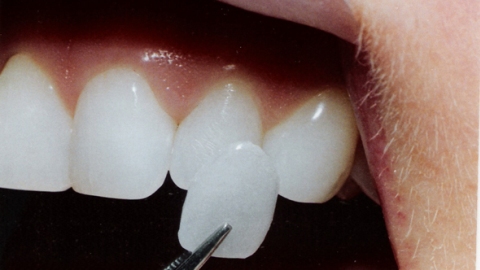

Veneers commonly called porcelain veneers and dental porcelain laminates, are thin layers of porcelain or resin composite restorative materials placed on the surface of a tooth to improve its appearance. This dental procedure is best used on patients with chipped, stained, worn and misaligned teeth. The great thing about having veneers is that they are highly resistant to staining and may last up to a decade. Getting dental veneers

requires three trips to the dentist, with the first visit for initial consultation, the second and third for making and applying the veneers.